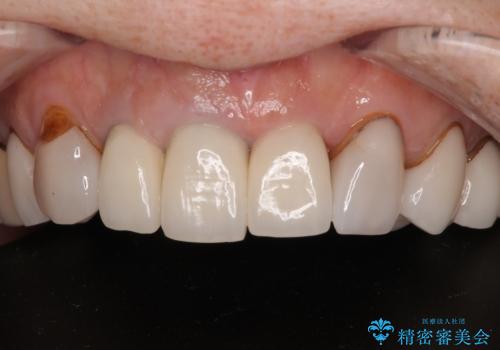

- 前歯のセラミックが欠けたり色調が不揃いであったりすることを気にして来院された患者様です。

20年以上前から、むし歯になったり詰め物が欠けたりする度に部分的に処置を行ってきたそうですが、この際統一感のある前歯にしたいとのことで、上顎前歯9本をオールセラミッククラウンによる補綴治療を行うこととしました。

色調が統一されるだけでなく、歯肉ラインに見えていた茶色の境目も綺麗に改善されました。